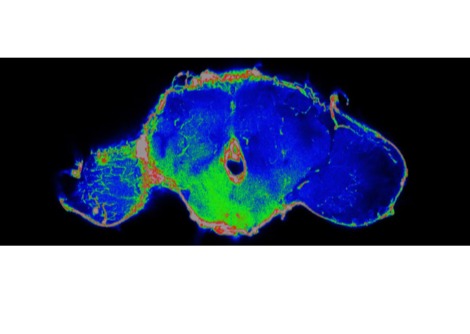

وفي عام 2025 أضافت لجنة نوبل فصلًا جديدًا إلى هذا التاريخ المجيد، إذ منحت جائزة نوبل في الطب لثلاثة علماءٍ أسهموا في كشف أسرار "التسامح المناعي المحيطي" — تلك الآلية الدقيقة التي تحفظ توازن جهاز المناعة بين الدفاع عن الجسم ومنع مهاجمة أنسجته الذاتية. كان هذا الاكتشاف ثمرة عقودٍ من البحث والتجريب، ومثّل تحوّلًا جذريًّا في فهم الطب الحديث لأصل الأمراض المناعية الذاتية. وقد جاء هذا الإنجاز تتويجًا لأعمال فريد رامزدل وشيمون ساكاجوتشي وماري برونكاو الذين كُرِّموا على إسهامهم في حل أحد أكثر ألغاز جهاز المناعة تعقيدًا، وهو كيف يستطيع هذا النظام المعقّد أن يدافع عن الجسم ضد الفيروسات والبكتيريا والخلايا السرطانية من غير أن ينقلب على نفسه ويدمّر خلاياه السليمة.